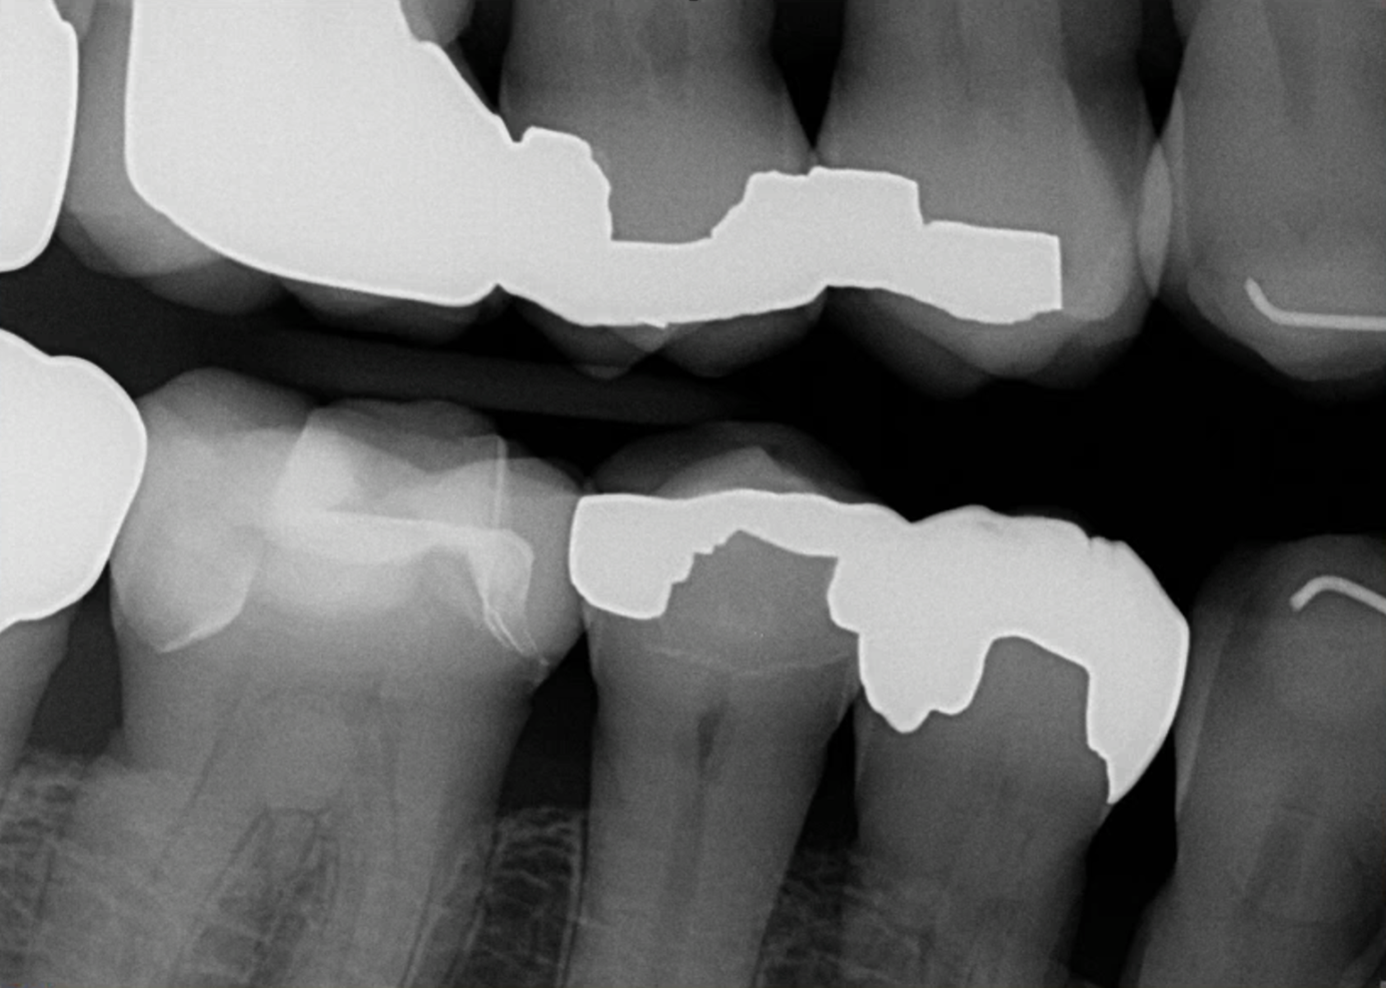

A patient presented on an urgent basis with a fractured buccal cusp of the mandibular second premolar (Figure 32). The tooth had a large MOD amalgam restoration, and the patient fortunately brought the fractured cusp fragment with them. Cuspal fractures of this type are common in teeth restored with amalgam or in teeth with thin, unsupported cusps under bonded restorations. Over time, occlusal forces flex the cusps, leading to crack initiation along the stress plane until catastrophic fracture occurs.

The ideal long-term management of this tooth would involve removing the amalgam, evaluating the remaining tooth structure, and placing a cuspal coverage restoration (e.g., indirect bonded onlay or full-coverage crown). However, given the urgency of the appointment and the patient’s desire for a quick, esthetic solution, a decision was made to re-attach the fractured cusp using an adhesive approach. This would immediately eliminate sensitivity, restore esthetics, and buy time before definitive treatment.13

Because the fractured piece fit precisely, occlusal adjustment was unnecessary after rubber dam removal. The fracture line was polished until nearly invisible, resulting in an immediate functional and esthetic improvement (Figure 37 through Figure 40).

(37.) Fractured cusp after adhesive bonding and polishing of the finish line, resulting in a smooth and seamless transition and 25-month follow up radiograph where the adhesively bonded fracture line is visible.

Figure 37

(38.) Fractured cusp after adhesive bonding and polishing of the finish line, resulting in a smooth and seamless transition and 25-month follow up radiograph where the adhesively bonded fracture line is visible.

Figure 38

(39.) Fractured cusp after adhesive bonding and polishing of the finish line, resulting in a smooth and seamless transition and 25-month follow up radiograph where the adhesively bonded fracture line is visible.

Figure 39

(40.) Fractured cusp after adhesive bonding and polishing of the finish line, resulting in a smooth and seamless transition and 25-month follow up radiograph where the adhesively bonded fracture line is visible.

Figure 40